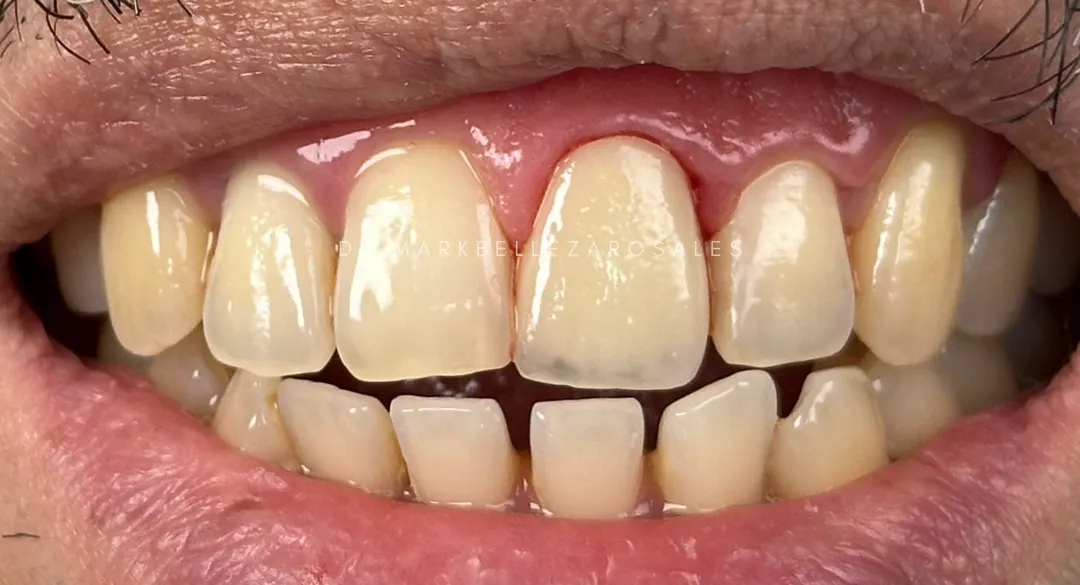

A zirconia crown is a tooth-colored dental cap used to restore a damaged, weakened, or heavily filled tooth. It provides exceptional strength, protects the remaining tooth structure, and offers a natural appearance while allowing you to chew and smile with confidence.